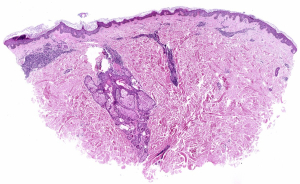

• Se realizó una biopsia de 4mm de una placa en abdomen izquierdo observándose un infiltrado dérmico perivascular y perianexial superficial sin alteraciones epidérmicas (Figuras 4 y 5). El estudio inmunohistoquímico ha mostrado positividad de marcadores de línea B (CD79a y CD20, Figura 6) y negatividad para CD138 (Figura 7). El índice proliferativo es bajo.